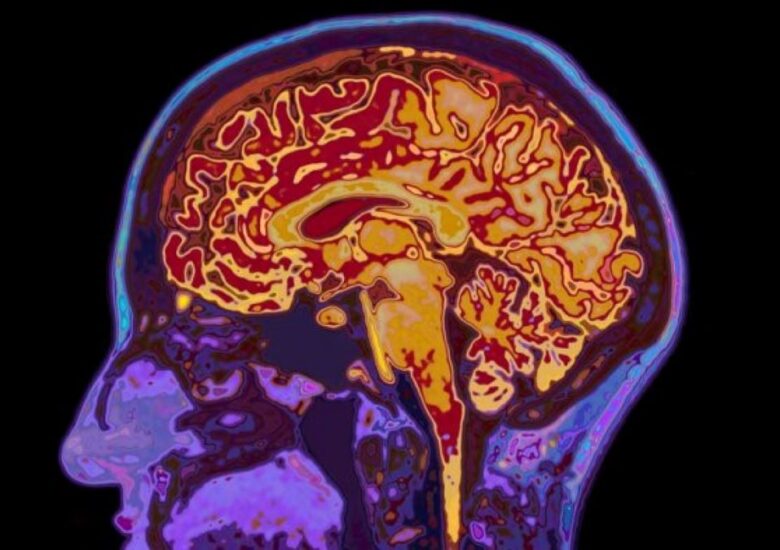

Când scleroza multiplă atacă măduva spinării

Leziunile măduvei spinării sunt mai frecvent observate în formele progresive de scleroză multiplă și pot duce la un risc crescut de dizabilitate. Aproape toți cei care suferă de scleroză multiplă